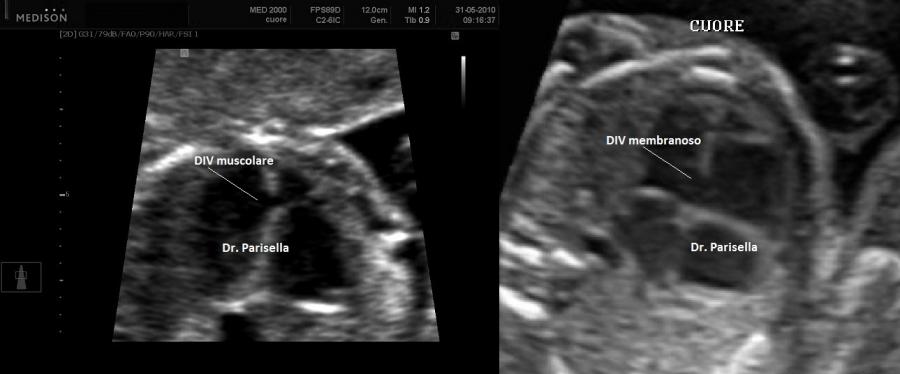

Possono essere associate cardiopatia congenita (Tetralogia di Fallot), anomalie renali e dismorfismi come micrognazia ed orecchie basse. Possono essere presenti altre anomalie scheletriche come ipoplasia omero, ulna e femore, piede torto (equino-varo), displasia congenita dell'anca.